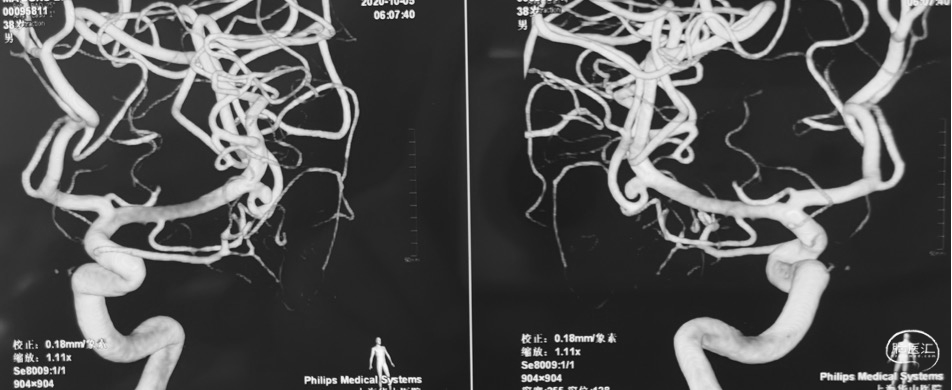

术前DSA

右侧

左侧